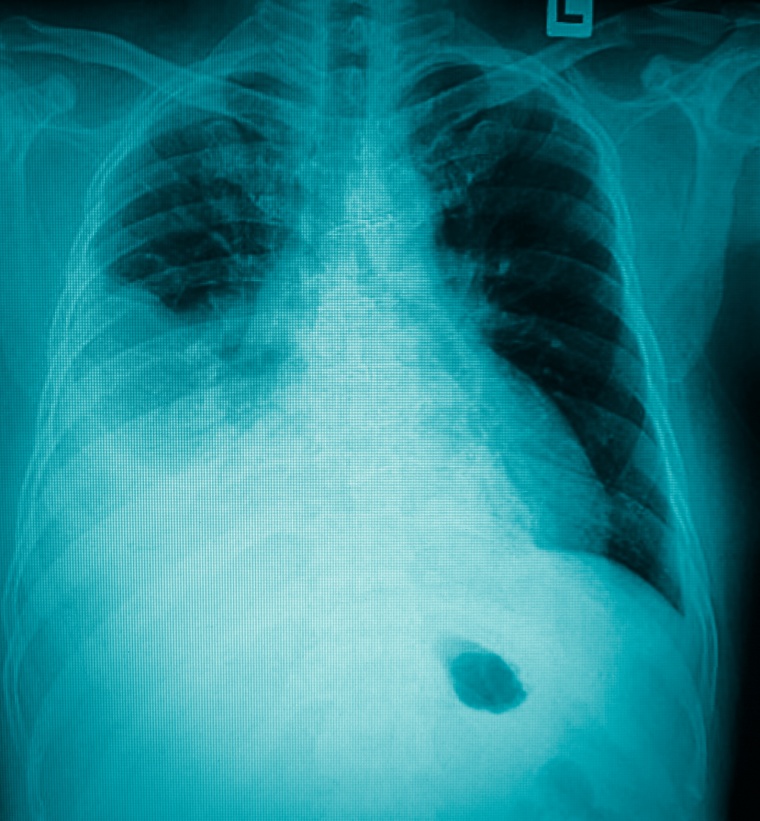

Die COVID-19 Erkrankung kann für Patienten einen sehr unterschiedlichen Verlauf nehmen. Für Mediziner ist es sehr hilfreich früh zu erkennen, welchen COVID-19-Patienten ein Lungenversagen droht. Diese Patienten könnten dann gezielt intensiv überwacht werden. Im Gegenzug können Patienten ohne Risikomerkmale auf Normalstation oder sogar zu Hause behandelt werden. Somit können Plätze auf Intensivstationen geschont und denjenigen zugewiesen werden, die sie wirklich brauchen. In einer Studie haben Wissenschaftler des LMU Klinikums München nun Biomarker gefunden, die genau diese Unterscheidung ermöglichen. Die Ergebnisse wurden jetzt im Journal of Allergy and Clinical Immunology publiziert.

Die meisten Menschen erkranken nach einer Infektion mit dem Virus Sars-CoV-2 nur leicht und erholen sich rasch. Bei etwa 5 % der Patienten kommt es aber zu einem schweren Erkrankungsverlauf mit Atemnot. Einige dieser Patienten müssen auf der Intensivstation künstlich beatmet werden. Bei einer schnell steigenden Zahl an Infektionen könnten so die Kapazitäten der Intensivstationen überlastet werden.

Es stellte sich heraus, dass sie alle erhöhte Werte eines Markers für Entzündungen, IL-6, im Blut aufwiesen. Mehr noch: „Ein IL-6-Wert von über 80 Pikogramm/Milliliter sowie ein CRP-Wert über 9,7 Milligramm/Deziliter während der Erkrankung sagte das spätere Lungenversagen mit hoher Genauigkeit voraus“, erklärt Dr. Tobias Herold. Das Risiko für ein Lungenversagen war für Patienten mit erhöhten Werten um ein Vielfaches gesteigert. Es besteht international ein großer Bedarf an solchen Erkenntnissen und das wissenschaftliche Interesse ist aktuell groß. Unklar ist weiterhin, ob IL-6 ein zentraler Faktor des ausufernden Krankheitsgeschehens in der Lunge ist oder lediglich ein Marker der Krankheitsaktivität.